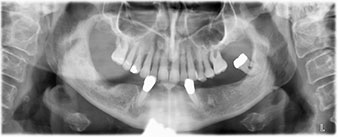

La patiente âgée de 64 ans présente une denture résiduelle des dents 38, 33 et 43 et une prothèse amovible mandibulaire stabilisée par crochets (Fig. 1 et 2).

Le traitement des lésions parodontales et l'extraction au maxillaire devront être réalisés plus tard car la patiente est enseignante et doit s'occuper des examens de fin d'année. Elle ne pouvait ni manger, ni parler correctement car la prothèse provisoire, très fragile, se fracturait régulièrement sous les moindres contraintes.

Après lui avoir expliqué les différentes options de traitements, la patiente a choisi l’extraction de la denture résiduelle à la mandibule, un implant posé immédiatement (Bredent Medical) et le traitement par la méthode All-on-four au cours duquel la prothèse fixe provisoire est vissée sur quatre implants le jour même de l'intervention. L'objectif étant d'intervenir sur la patiente le vendredi afin qu'elle puisse participer aux examens oraux le lundi suivant.